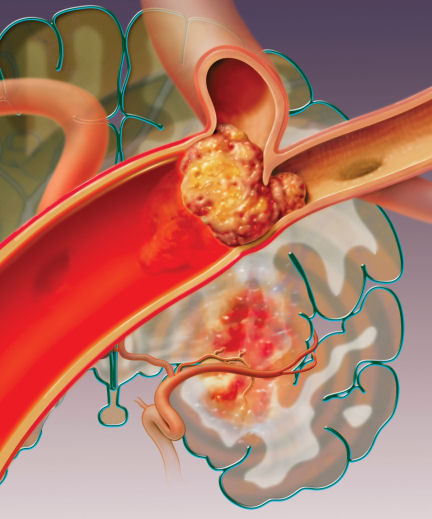

Anderson Holness had had an ischemic stroke, the type caused by a blocked blood vessel in the brain. The stroke killed some of her brain tissue by cutting it off from its oxygen and nutrient supplies.

Still, there is currently only one drug treatment approved by the Food and Drug Administration for use at the time an ischemic stroke occurs. That drug is tissue plasminogen activator (tPA), given intravenously to dissolve blood clots. FDA approved the famous “clot buster” in 1996.

Treatment with tPA saves many patients—as it did Anderson Holness—by opening obstructed blood vessels in their brains. But the drug has severe limitations. Doctors have to first do a computerized tomography scan to make sure that the person isn’t experiencing a bleeding stroke, which tPA would make worse. And the clot-busting drug must be administered within 3 hours of the onset of a stroke—which isn’t always possible because many delays occur on the way to emergency treatment. After 3 hours, the risk of bleeding outweighs the potential benefit of tPA, at least according to current medical judgment. The potential complications have made emergency room physicians reluctant to give tPA, says Costantino Iadecola, chief of the division of neurobiology at Weill Cornell Medical College in New York City.

Still others are using ultrasound to make tPA more effective. In a small clinical study published in 2004, Andrei Alexandrov, now at the University of Alabama at Birmingham, found that applying ultrasound through the skull triples the effectiveness of tPA in dissolving ischemic-stroke clots. The sound waves agitate the stagnant blood in the blood vessels affected by the stroke, Alexandrov says, allowing tPA to better reach and penetrate the blood clot. “It’s like a spoon that stirs sugar in a cup of tea,” he says.

More recently, Alexandrov has been working with ImaRx Therapeutics of Tucson, Ariz., which makes tiny, gas-filled bubbles by enclosing minute quantities of perfluoropropane in fatty shells that are similar to cell membranes in humans. Administered intravenously, the bubbles aren’t dangerous, he says, because perfluoropropane is chemically inert and present in only small amounts. But when the bubbles reach the site of stroke damage, ultrasound vibration makes them oscillate or even explode. This further agitates the stagnant blood around a clot, Alexandrov says. In February, he told the International Stroke Conference in San Francisco of early success combining tPA, ultrasound, and gas bubbles to dissolve clots in stroke patients.